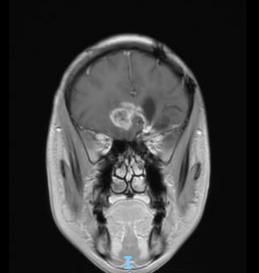

44歲的郭先生(化姓)為膠質(zhì)瘤復(fù)發(fā)患者,復(fù)查發(fā)現(xiàn)顱內(nèi)占位進(jìn)行性進(jìn)展1周,MRI檢查提示瘤體已累積到胼胝體,且瘤體位置較深,手術(shù)難度極高。面對(duì)這一挑戰(zhàn),王虎教授團(tuán)隊(duì)決定采用多種先進(jìn)技術(shù)輔助手術(shù),其中最為引人注目的就是首次引入的細(xì)胞級(jí)顯微鏡EndoSCell?。該設(shè)備是目前全球唯一實(shí)時(shí)在體細(xì)胞級(jí)顯影的儀器,可以輔助醫(yī)生從細(xì)胞層面區(qū)分腫瘤組織與正常組織,從而做到細(xì)胞級(jí)精準(zhǔn)切除。

患者術(shù)前核磁影像